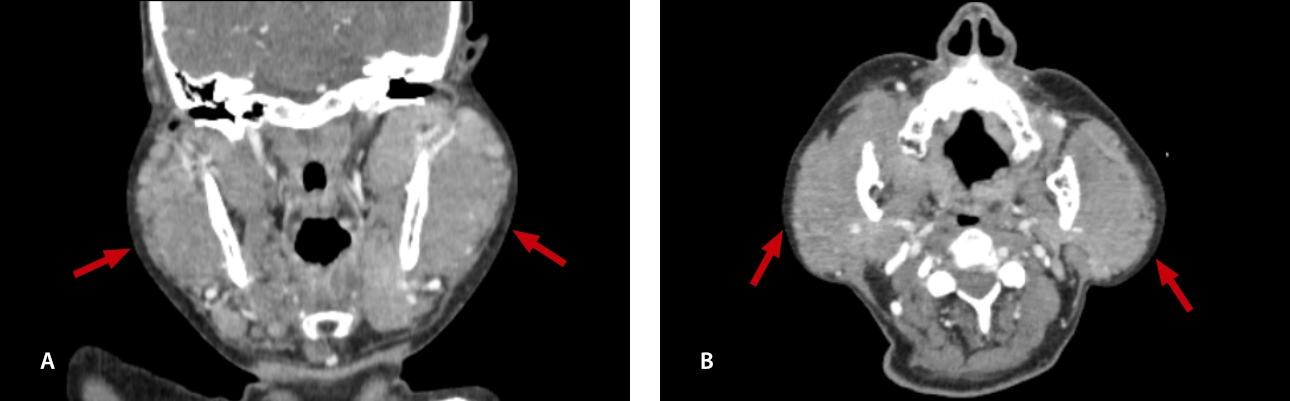

lymphoma-simulator-fig8-pc

Fig. 8: Contrasted CT scan: (A) axial section (B) coronal reconstruction: shows heterogeneous lacrimal glands, enlarged in size (red arrows).

lymphoma-simulator-fig9-pc

Fig. 9: Contrasted CT scan: (A) axial section shows paravertebral conglomerate (bulky mass) (white arrows), (B) coronal reconstruction shows bilateral cervical lymphadenopathy (black arrows).